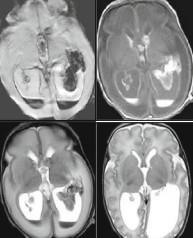

Term Severe Injury - MRI

Loss of Posterior Limb Internal Capsule “PLIC Sign”

T1 Normal Myelin Signal in

Term HII

Acute Injury

Subacute Injury

Lack (or delay) of return to normal PLIC myelin signal predicts poorer outcome.

Term HIE Patterns driven by metabolic need. Patterns determined

by duration and severity of injury.

Profound Insult and Short Duration: Metabolic Demand

 Insult Pattern is Driven by Metabolic Need = Myelination

 Grey Matter greater [GLU], results in greater excitotoxic injury

 Basal ganglia, thalamus, perirolandic cortex, variable visual cortex, dorsal brainstem

Term HII Late Appearance HIE

Severe Asphyxia – Chronic

Acute/Subacute Injury

Early Day 4-10

Clinical: “toe walker” (spasticity with variable developmental delay and/or cognitive difficulties)